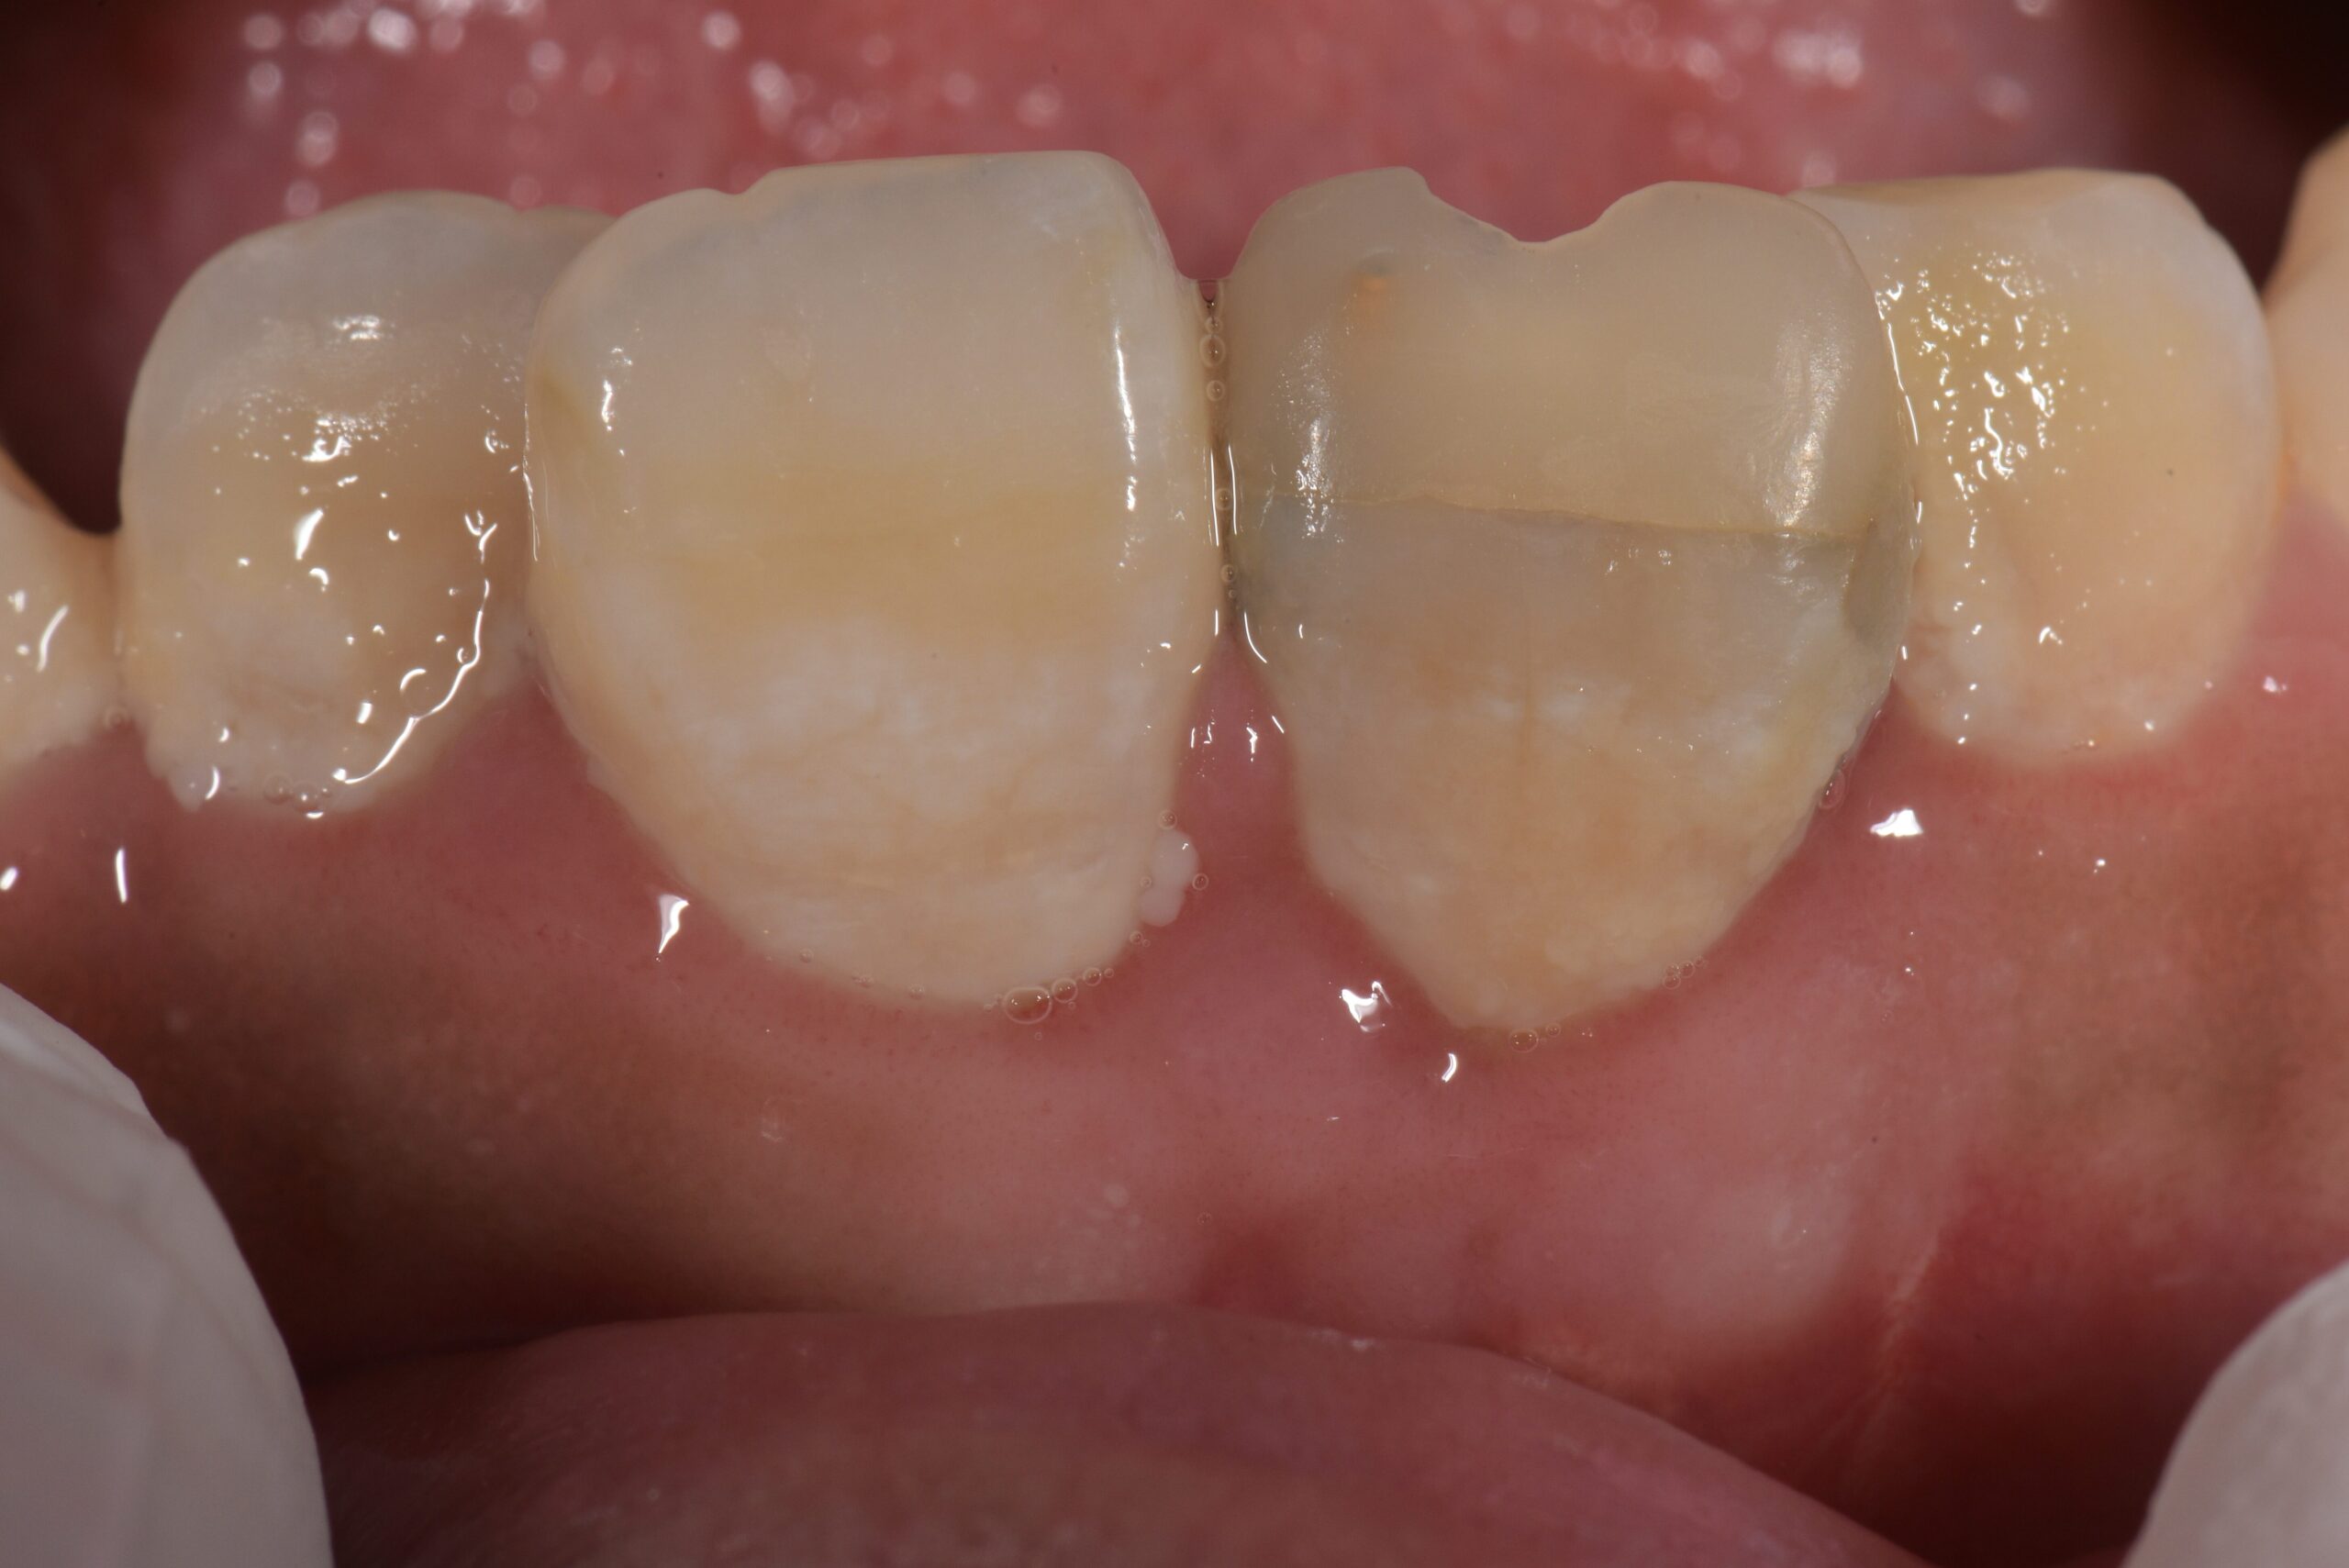

治療後

宇部市内の未成年の学生さんということもあって、今回はなんとか自由診療は使わずに全て自己負担分のない保険診療内で治療をしております。

被せ物の色と患者さんの歯の色に違いはありますが、これは保険診療に使う被せ物の色は決まったものしかないためです💧

ただ、最初の変色した歯の色に比べたらだいぶ変わって、気にならないと言って頂けました😅

(保険診療では歯の色は決まったものしか使えないので、気になる場合は将来的に自由診療での被せ物をお勧めしています)

今回の治療のメインは歯の保存で、自然で審美的な歯にするのが目的ではなかったので

費用を抑えつつ歯を保存できただけでも、今回の治療結果は患者さんも術者側も満足できる結果になりました( ^ω^ )